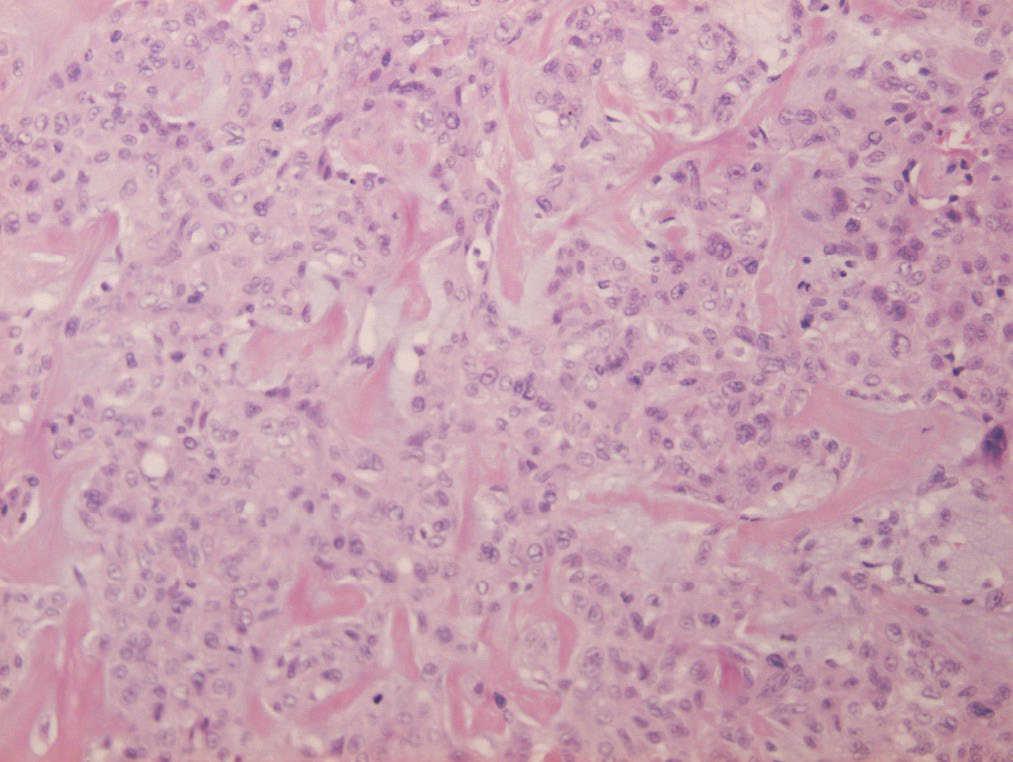

La formación nodular que se envía para estudio anatomopatológico; mide 1,8 x 1,5 cm, es de consistencia firme y coloración amarillenta. Microscópicamente se corresponde con una masa multinodular, localizada en la hipodermis, mal delimitada, que no está encapsulada e infiltra grasa en algunas áreas (fig. 1) Está constituida por células de citoplasma amplio y eosinófilo, con tendencia a formar nódulos con haces gruesos de fibras colágenas. Los núcleos son grandes y redondos u ovalados. Se observan signos de malignidad como atipia, pleomorfismo celular e invasión perineural. Otras zonas muestran un patrón de crecimiento fusiforme y un estroma con cambios mixoides (fig. 2). Con técnicas de inmunohistoquímica, las células tumorales expresan fuerte positividad para vimentina, queratinas AE1/AE3 y EMA, y positividad focal para CD34, actina y citoqueratina 7 (fig. 3). No se observa inmunoexpresión de CK20, CD31 ni S-100. El índice proliferativo (Mib-1) es bajo, del 5%. Con estos datos se establece el diagnóstico de sarcoma epitelioide de tipo proximal de vulva.

Figura 2.La celularidad predominante es epitelioide con producción de colágeno (HE, x200).